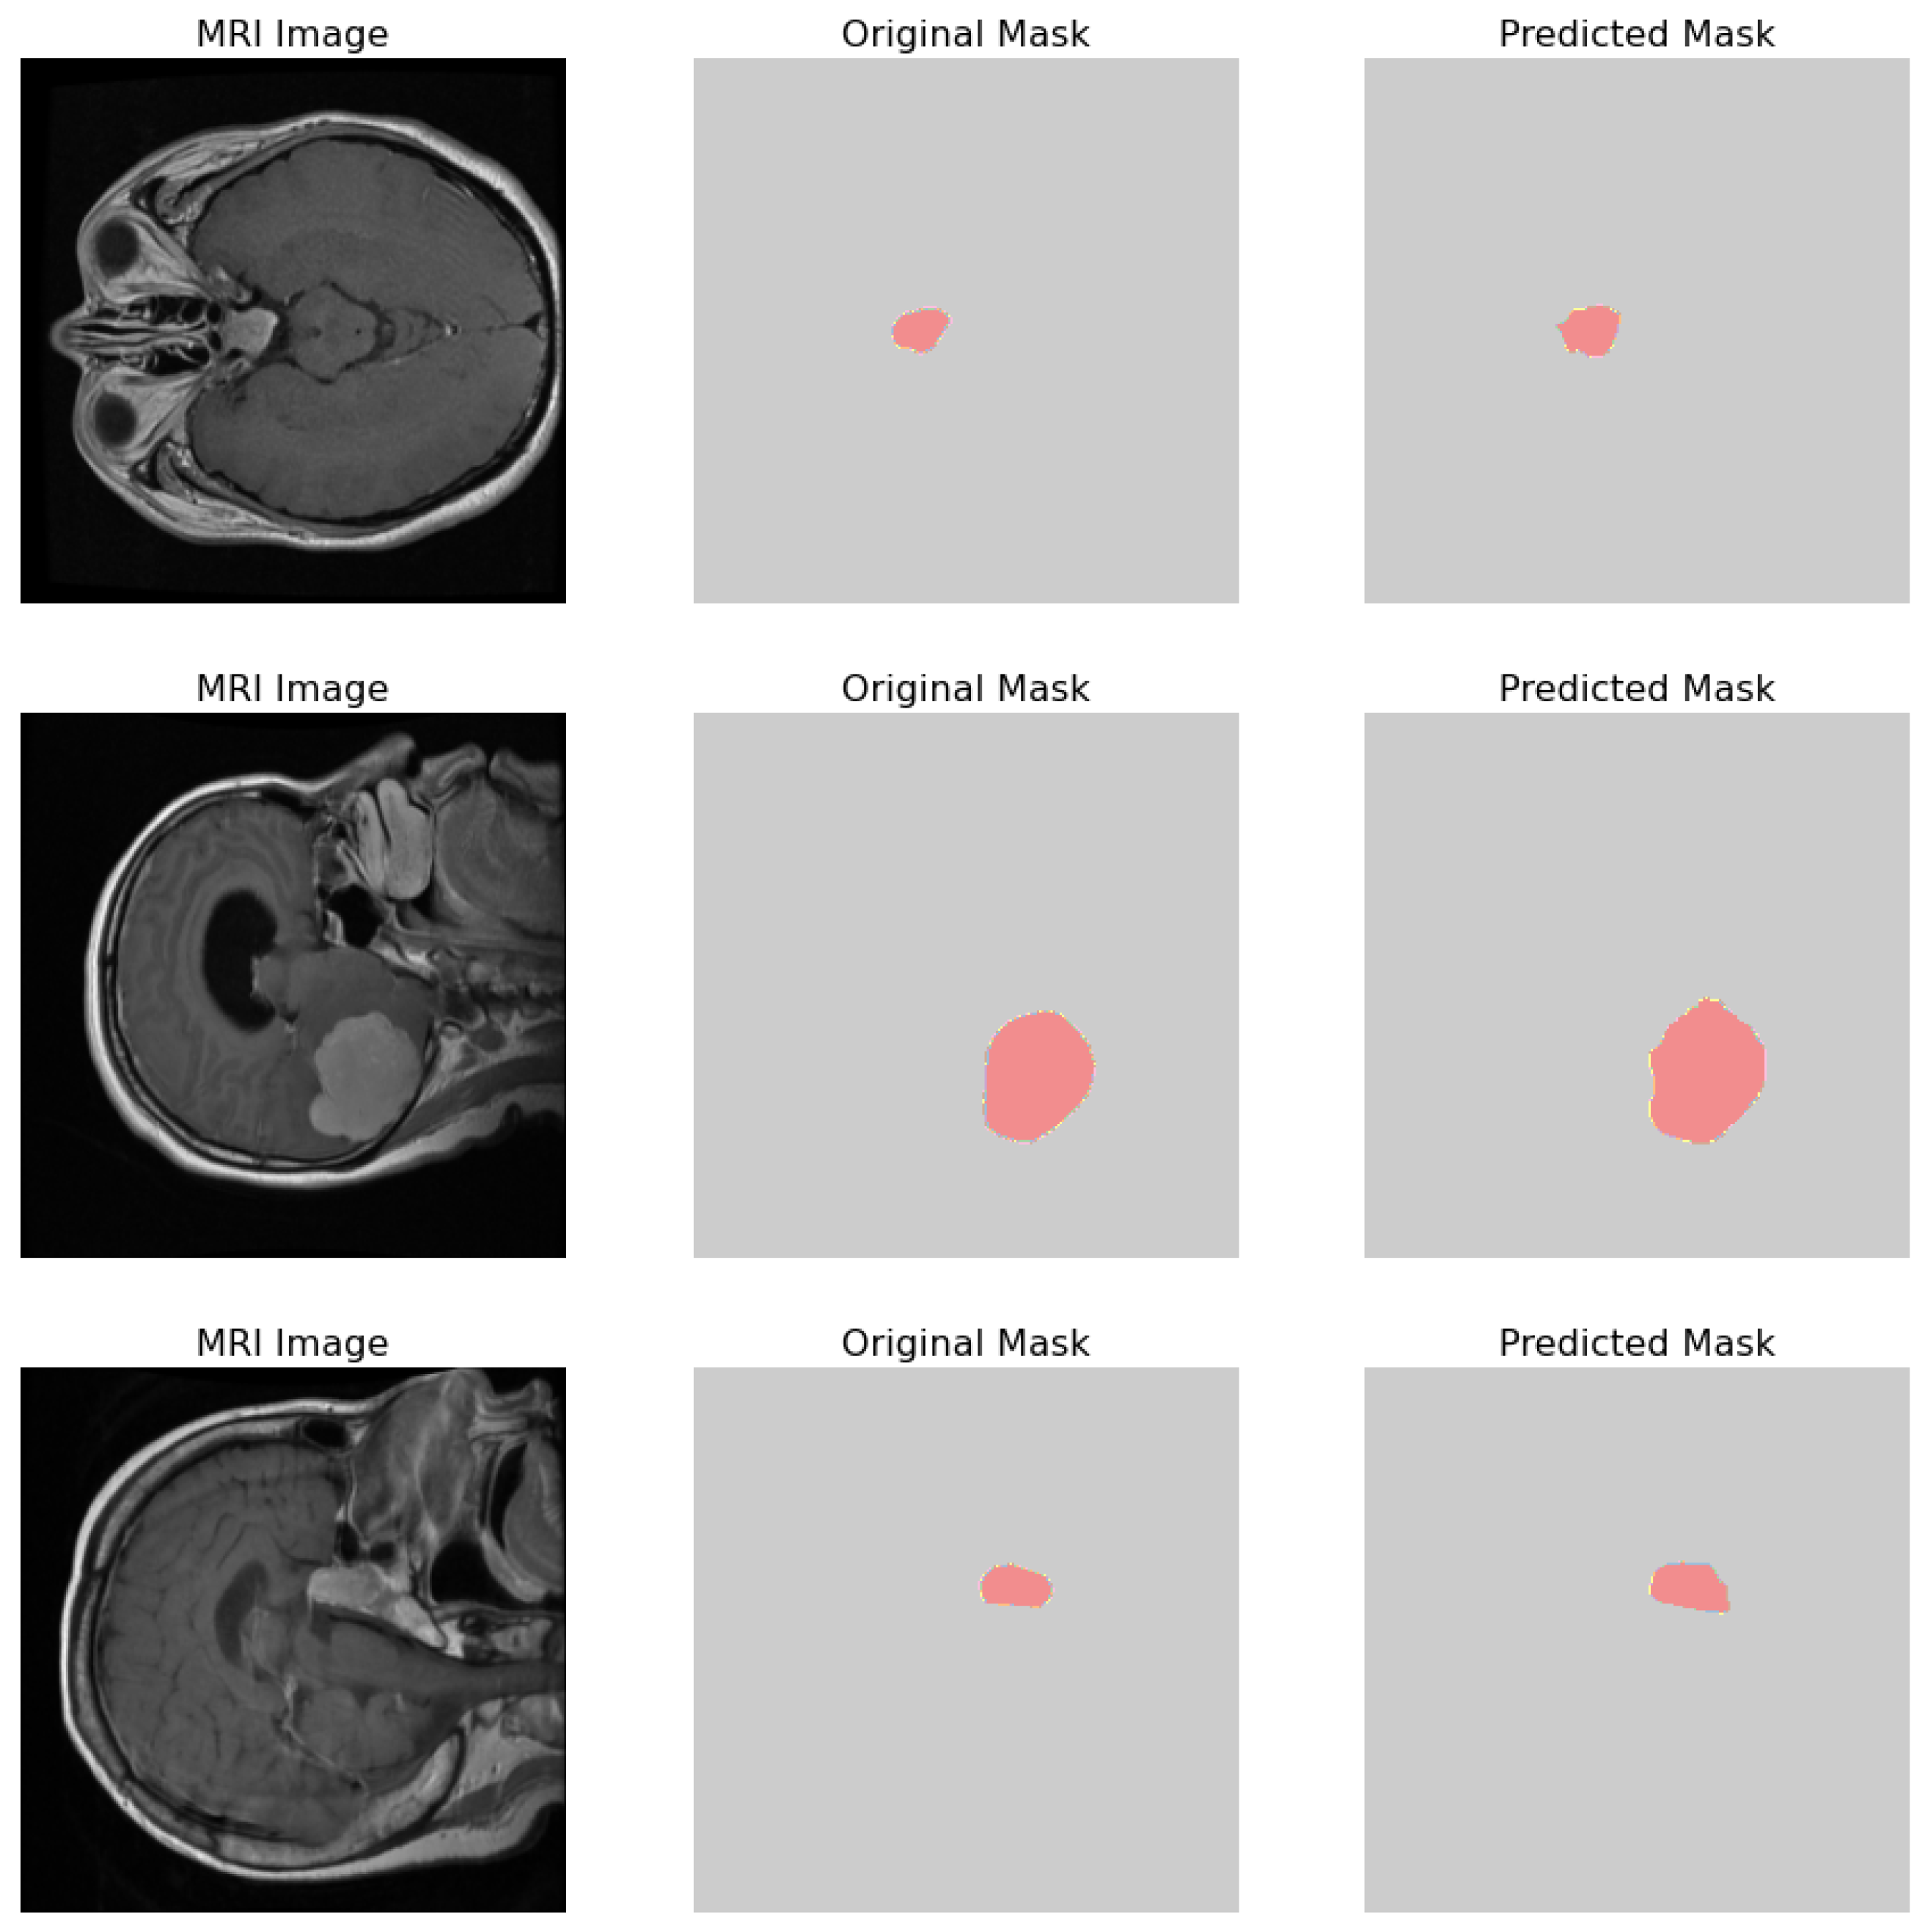

- Original Image: The pipeline receives the MRI scan as its initial input, showcasing a comprehensive cross-sectional view of the patient’s brain and potential pathological features.

- Ground Truth Mask: Next to the original image is the ‘Ground Truth Mask’, meticulously annotated by clinical experts to delineate the regions of clinical significance, such as lesions or tumors.

- Predicted Mask: The segmentation branch of our pipeline then predicts a mask, endeavoring to replicate the expert annotations by encapsulating the region of interest highlighted in the MRI scan.

- Predicted Class: Simultaneously, the classification branch assigns a ‘Predicted Class’ to the scan. The labels, denoted by integers (0, 1, 2), classify the scan into categories that reflect the model’s interpretation of the underlying pathology.